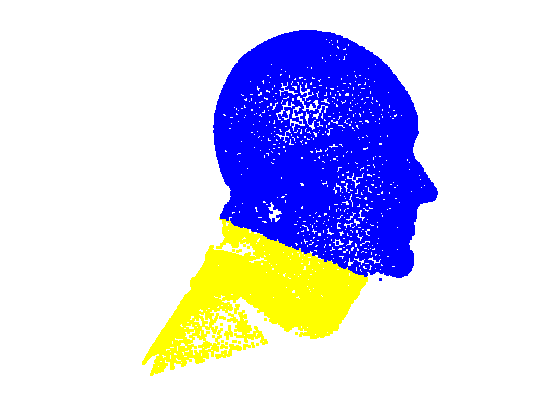

5.3 Face and cranium segmentation

Fitting a sparse model to the head scan data normalises its pose to frontal. Since we use landmarks that localise the majority of the facial area (rather than just inner eyes and nose), we can reliably position a scale-adaptive mesh cropping plane. We choose a distance below the chin landmark, that is some proportion of the face length, defined by the distance from the nasion landmark to the chin landmark. This gives a cropping plane that scale-adapts to the size of the head and it is aligned such that it is at some fixed angle (eg. 40 degrees, chosen experimentally) in the Y-Z plane. This is then used to remove the neck and shoulder area of the scan, as shown in Fig. 10.